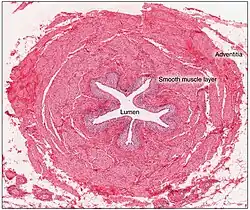

Histologie

Der Harnleiter zeigt den typischen Aufbau vieler Hohlorgane mit einer inneren Schleimhaut (Tunica mucosa), einer Muskelschicht (Tunica muscularis) aus glatter Muskulatur und einer äußeren bindegewebigen Verankerungsschicht (Tunica adventitia). Man nennt diesen Grundaufbau „häutig-muskulöser Schlauch“.

Die Schleimhaut weist fünf bis sieben Längsfalten auf.[6] Daher erscheint das Lumen im Querschnitt sternförmig. Die Falten sind Reservebildungen und verstreichen bei stärkerer Dehnung des Organs. Innen ist die Schleimhaut mit Urothel bedeckt. Darin sind die Zellen mehrreihig angeordnet und können so den Volumenschwankungen folgen. Es lassen sich drei Schichten unterscheiden: Die Basalzellen sind klein, würfelförmig und sitzen der Basalmembran auf. Sie sind die Reservezellschicht, von der die anderen Zellen abstammen. Die mittlere Zellschicht besteht aus drei bis sieben Zelllagen, den Intermediärzellen. Zum Lumen hin folgen schließlich die Deckzellen. Jede dieser kuppelförmigen Deckzellen überspannt mehrere Intermediärzellen, weshalb sie im Englischen auch als umbrella cells („Regenschirmzellen“) bezeichnet werden. Sie haben oft polyploide, manchmal auch zwei oder mehr Zellkerne. Sie sind durch Tight Junctions fest verbunden, so dass eine wasserdichte Barriere entsteht. Zudem ist die lumenseitige Zellmembran durch Intermediärfilamente, spindelförmige Vesikel, Einfaltungen und Mikrovilli modifiziert. Darüber hinaus gibt es hier spezifische Transmembranproteine, die Uroplakine. Diese Bildungen erwecken lichtmikroskopisch das Bild einer „Kruste“ (Crusta).[19] Die besondere Ausprägung der Zellmembran schirmt das darunterliegende Gewebe vor giftigen und hypertonen Substanzen im Urin ab. Das Urothel sitzt auf einer Bindegewebsschicht, die als „Eigenschicht der Schleimhaut“ (Lamina propria mucosae) bezeichnet wird. Hier sind auch Lymphozyten und Makrophagen eingelagert, welche der Abwehr von Krankheitserregern dienen.[20]

Die Muskelschicht kann in eine innere Schicht mit längs angeordneten Muskelzellen (Längsmuskelschicht, Stratum longitudinale) und eine äußere Schicht mit ringförmig angeordneten Zellen (Ringmuskelschicht, Stratum circulare) gegliedert werden. Im Bereich des Beckenteils des Harnleiters liegt der Ringmuskelschicht noch einmal eine (äußere) Längsmuskelschicht (Stratum longitudinale externum) auf. Diese Schichtung ist aber stark vereinfachend, in Wirklichkeit handelt es sich um spiralig angeordnete Muskelsysteme mit unterschiedlicher Steigung.[21][22] Die Muskelschicht ist beim Menschen 750 bis 800 µm dick.[22] Sie ist gut durchblutet und mit den kleinen Blutgefäßen verlaufen marklose Nervenfasern.[23]

Die Tunica adventitia oder kurz Adventitia ist eine Bindegewebsschicht mit zahlreichen Bündeln von Kollagenfasern, Fettzellen, mehrheitlich längs verlaufenden Blutgefäßen und größtenteils marklosen Nervenfasern.[24]